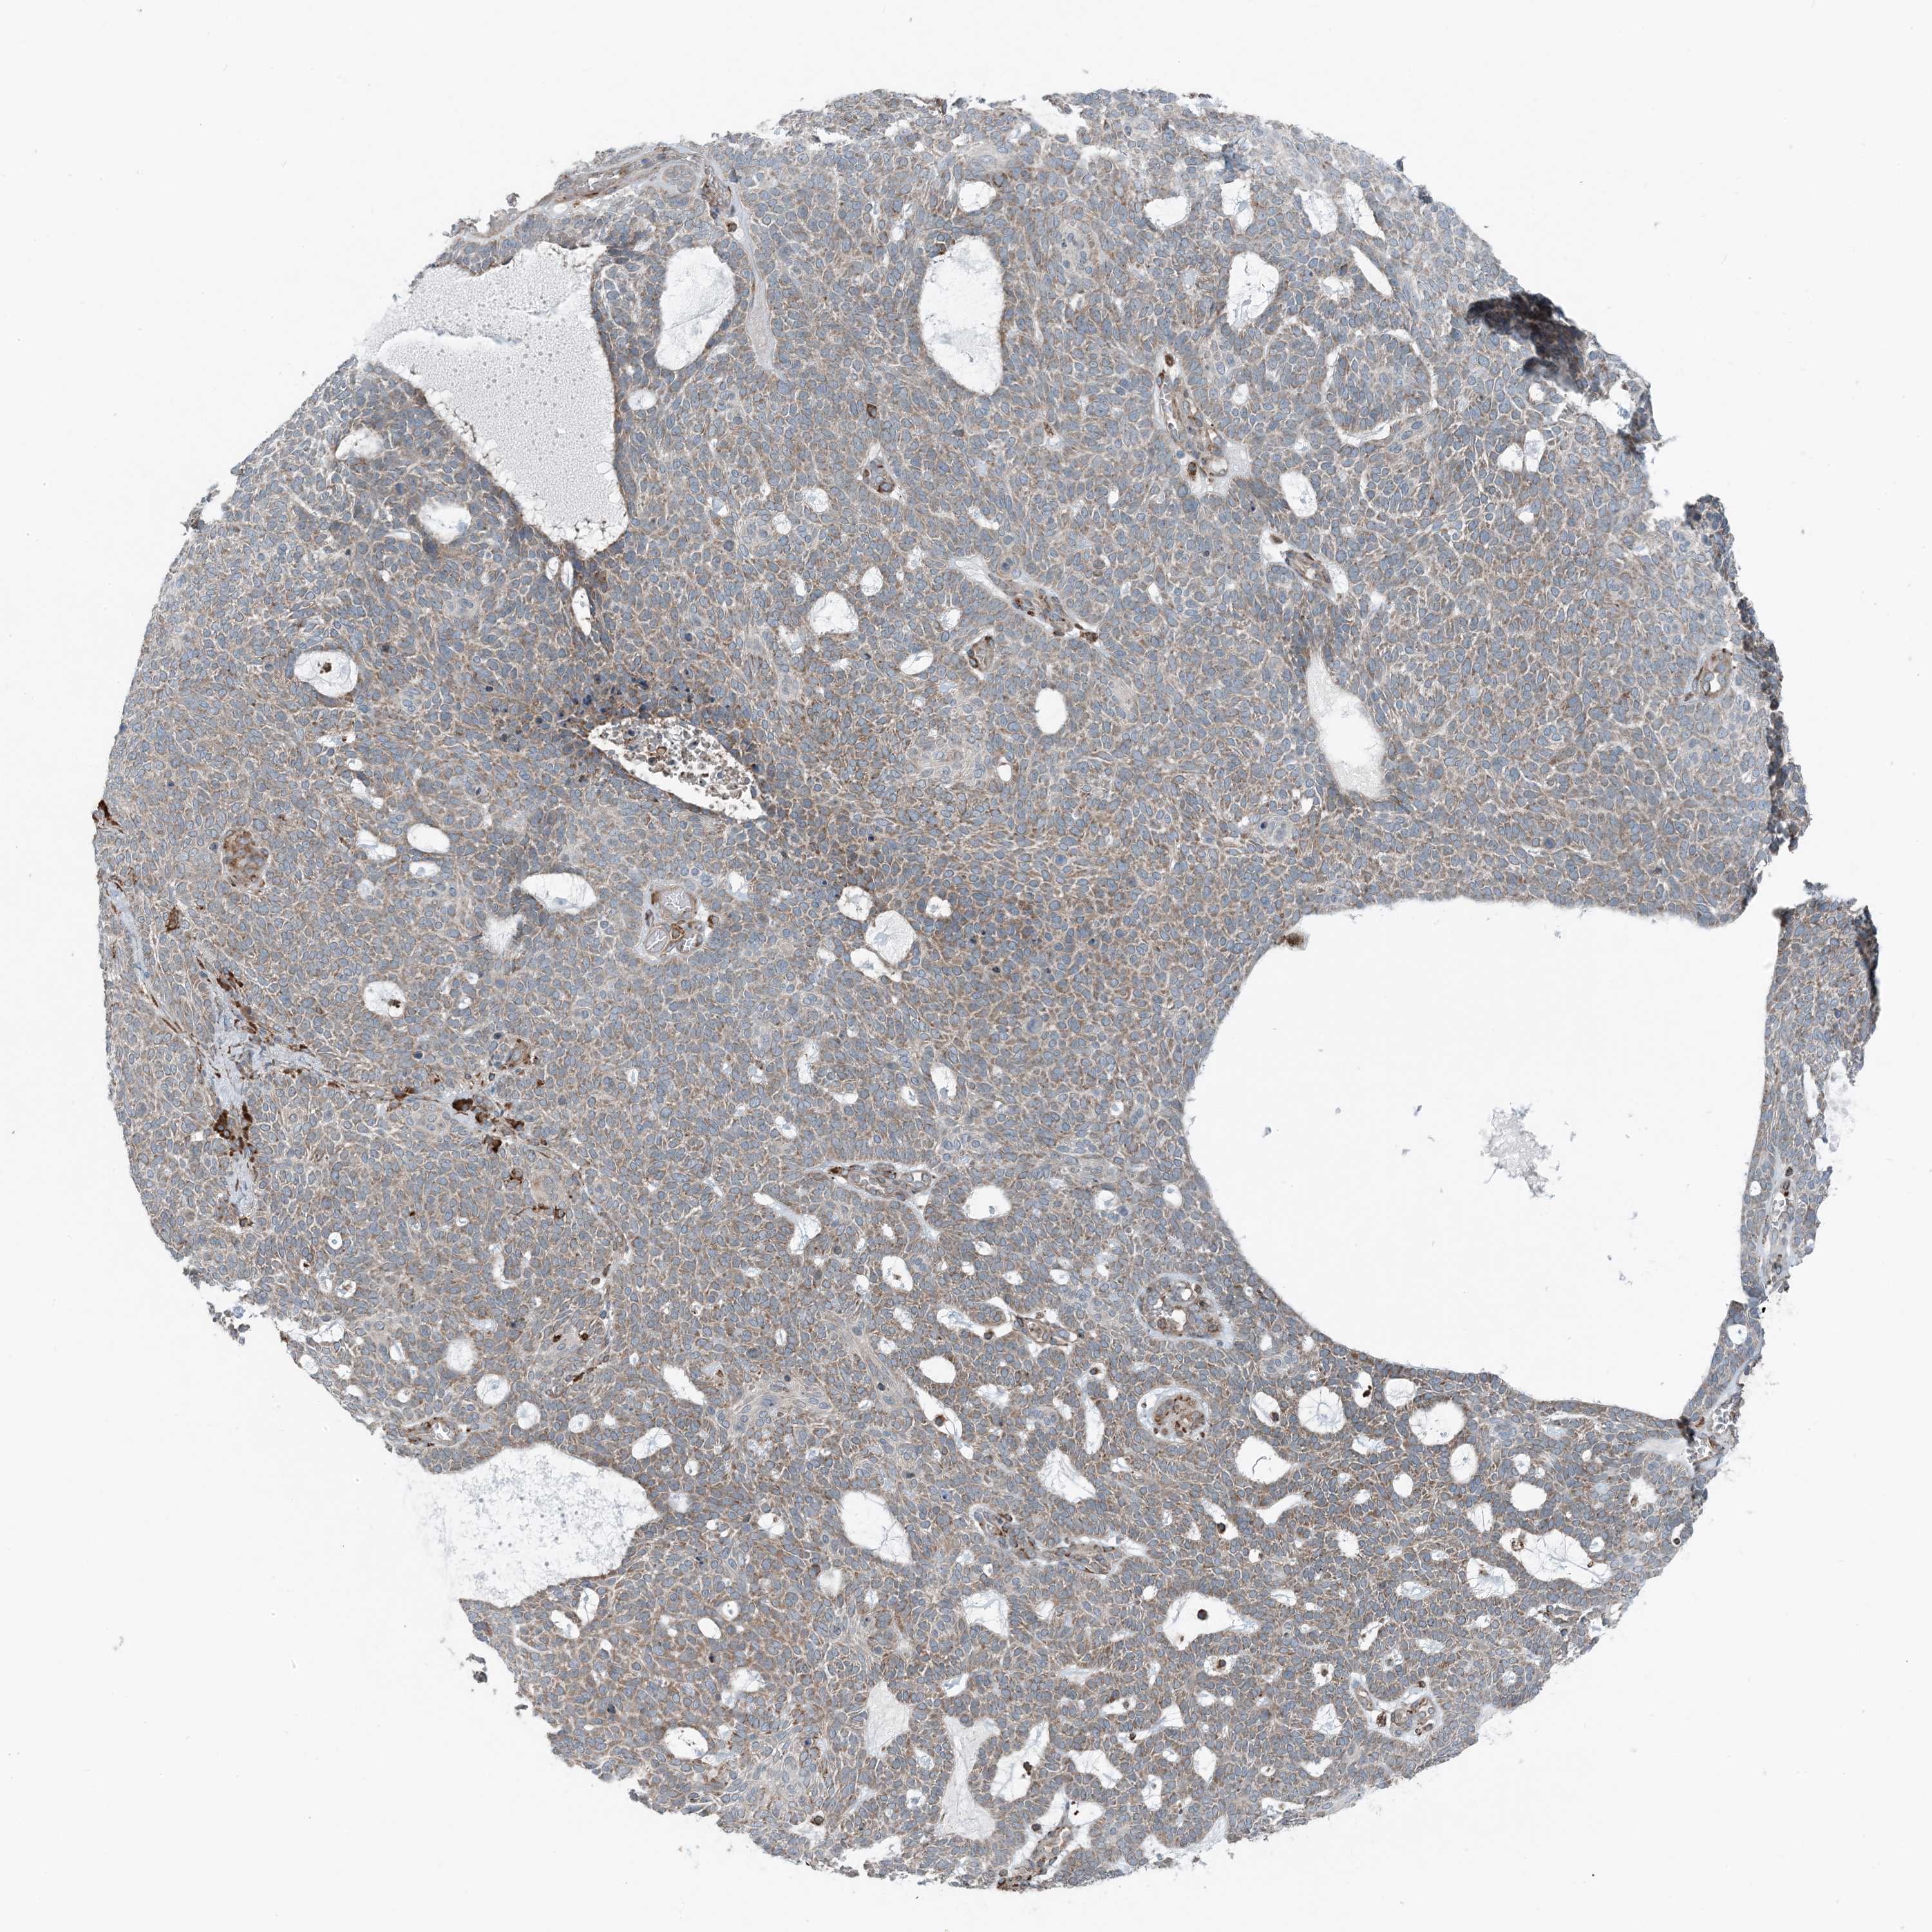

SKIN CANCER - Protein expressioni

A mouse-over function shows sample information and annotation data. Click on an image to view it in a full screen mode. Samples can be filtered based on level of antibody staining by selecting one or several of the following categories: high, medium, low and not detected. The assay and annotation is described here.

Each image is clickable and will lead to virtual microscopy that enables deeper exploration of all samples and also displays staining intensity scores, fraction scores and subcellular localization as well as patient and tissue information for each sample.

Antibody HPA035444

Staining

High

Medium

Low

Not detected

Intensity

Strong

Moderate

Weak

Negative

Quantity

>75%

75%-25%

<25%

None

Location

Nuclear

Cytoplasmic/membranous

Cytoplasmic/membranous,nuclear

Squamous cell carcinoma, metastatic, NOS

Squamous cell carcinoma, NOS